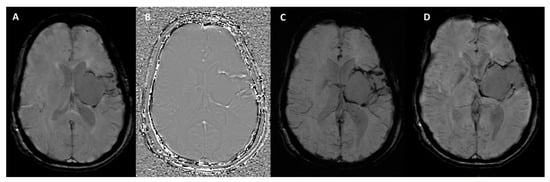

3. Technical Fundamentals of SWI

How Can Calcifications and Blood Be Differentiated on an SWI Phase Map?

- Yaghmaie, N.; Syeda, W.T.; Wu, C.; Zhang, Y.; Zhang, T.D.; Burrows, E.L.; Brodtmann, A.; Moffat, B.A.; Wright, D.K.; Glarin, R.; et al. QSMART: Quantitative susceptibility mapping artifact reduction technique. NeuroImage 2021, 231, 117701. [Google Scholar] [CrossRef]